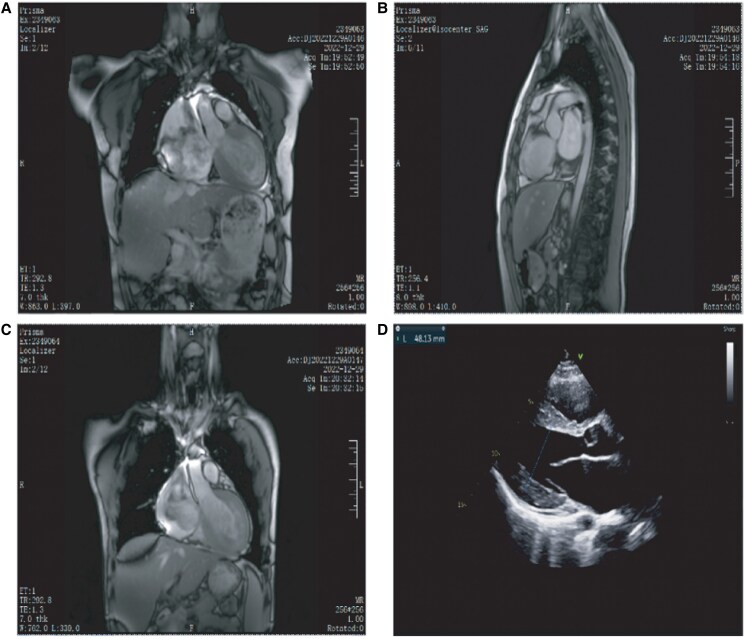

Background: Restrictive cardiomyopathy (RCM) is a relatively rare cardiomyopathy. We report a case of familial restrictive cardiomyopathy confirmed by myocardial biopsy and genetic testing.

Case summary: A 19-year-old male presented with recurrent syncope and cardiac arrest episodes over 1 year. Genetic testing identified a novel heterozygous insertion mutation (c.2489_2490insTTGCT, p.Q830Hfs*73) in the ACTN2 gene, altering a highly conserved amino acid sequence. Immunohistochemical analysis of endomyocardial biopsies revealed significantly elevated ACTN2 protein expression (77.34% positivity, H-Score 132.14). This mutation represents a likely pathogenic variant accounting for sudden cardiac deaths in multiple male family members.